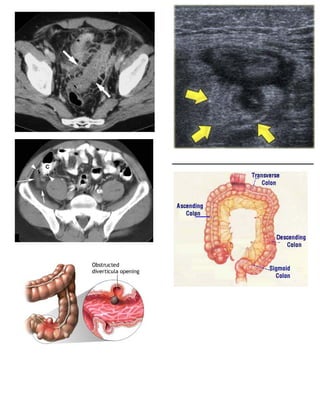

6. Radiology

2. ABDOMINAL CT WITH CONTRAST

1.   Best test to confirm Diverticulitis

(Complicated Diverticulitis)                    2.   Best test to identify complications

3.   Findings suggestive of perforation

1. Pericolic fat infiltration

2. Fascial thickening and muscle

hypertrophy

3. Arrowhead sign

1. Localized bowel wall

thickening

2. Bowel lumen

resembles arrow

3. Symptoms                                                                                           shape at diverticulum